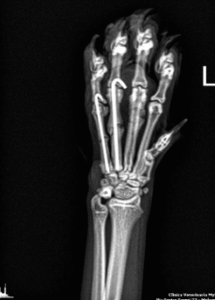

Chirurgia ortopedica

Chirurgia eseguita da specialisti utilizzata per trattare patologie ossee e articolari.

Gli interventi ortopedici sono procedure chirurgiche che trattano patologie dell’apparato muscolo-scheletrico, come fratture, lussazioni, displasie e problemi articolari. Si occupano di correggere deformità, riparare lesioni e migliorare la mobilità degli animali.

Fratture: Correzione e allineamento di fratture ossee.